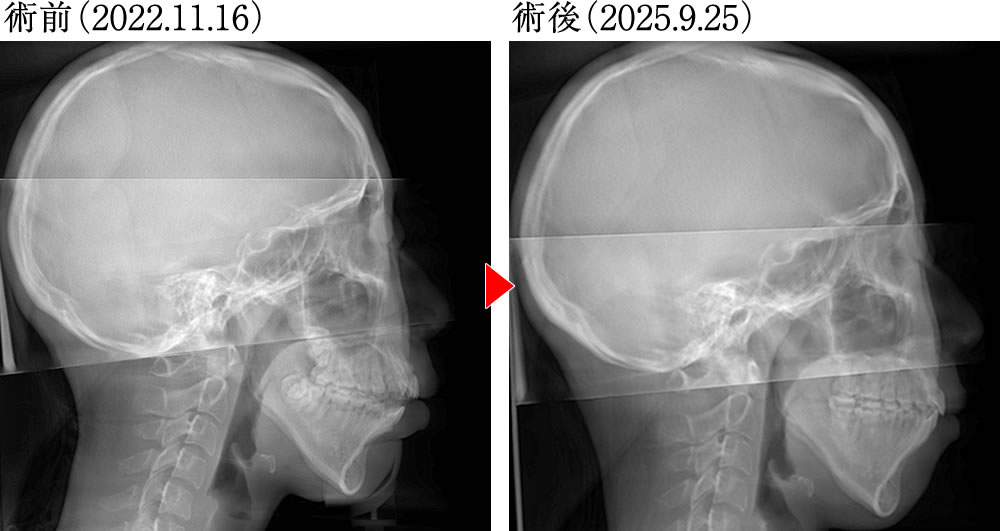

治療前後のレントゲン画像

術前は、前歯が噛み合わず、下顎が大きく後方回転した状態でしたが、術後は、前歯がしっかり閉じて噛み合うようになり、正しい被蓋関係の歯並びとなりました。また、下顎が前方回転して整ったことにより、口唇閉鎖時の唇の形態が改善され、舌骨も大きく前方に偏位しました。

下顔面高の変化

術前は、下顔面高(ANS–Me)が標準偏差を超えて77.4ありましたが、純粋な下顎の前方回転により、標準偏差内の75.5へと改善しました。

頭位の変化

術前は、強いスニッフィングポジションが認められましたが、術後は、標準頭位に近い姿勢へと改善しました。

スニッフィングポジション:頭部をやや前に出し、顔を少し上向きにした姿勢。